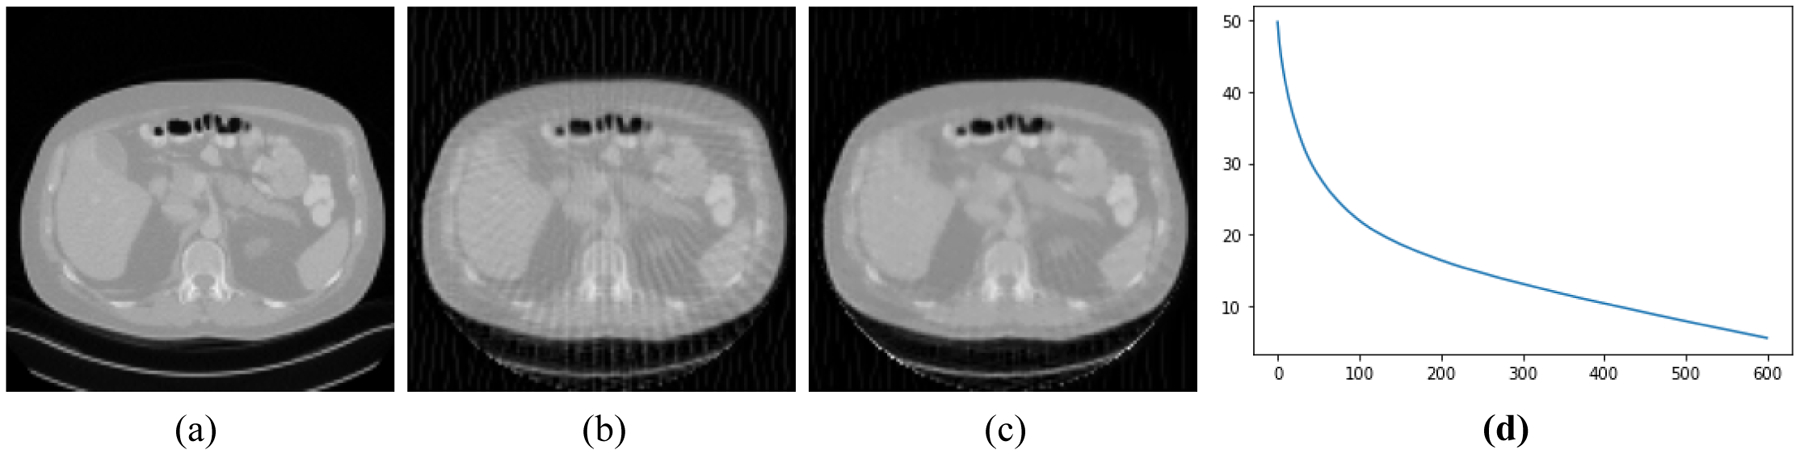

Background: Image reconstruction with under-sampled data is usually achieved by an iterative algorithm, which minimizes an objective function. The objective function commonly contains a data fidelity term and one or more Bayesian terms. A popular Bayesian term is the total variation (TV) norm of the image.

Methods: This paper suggests an addition Bayesian term that is generated by a neural network. This neural network is essentially a classifier. This classifier can recognize the artifacts caused by the incomplete data. This classifier is trained by patient images reconstructed by complete and incomplete data sets. This newly introduced Bayesian term is referred to as the CNN score, which is a real number in (-∞, ∞).

Results: Patient studies show the good correlation between the CNN score and the severeness of the artifacts due to the incomplete measurements.

Conclusions: A neural network can extract features from images that are suffering from incomplete measurements and convert the features into a CNN score. An iterative image reconstruction algorithm can be developed to minimize this CNN score to suppress the artifacts in the reconstructed image.